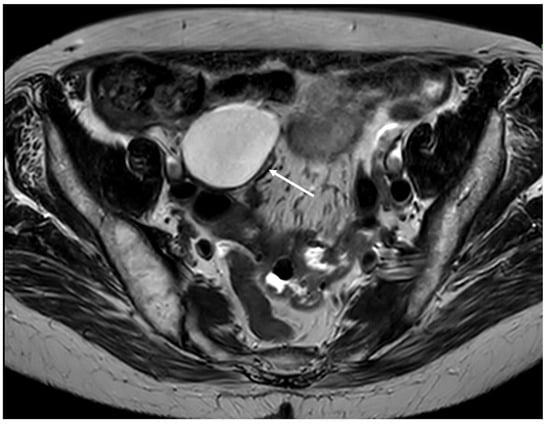

Figure 4. Cystic dilatation of the appendix (mucocele) (arrow) (MRI, axial plane).